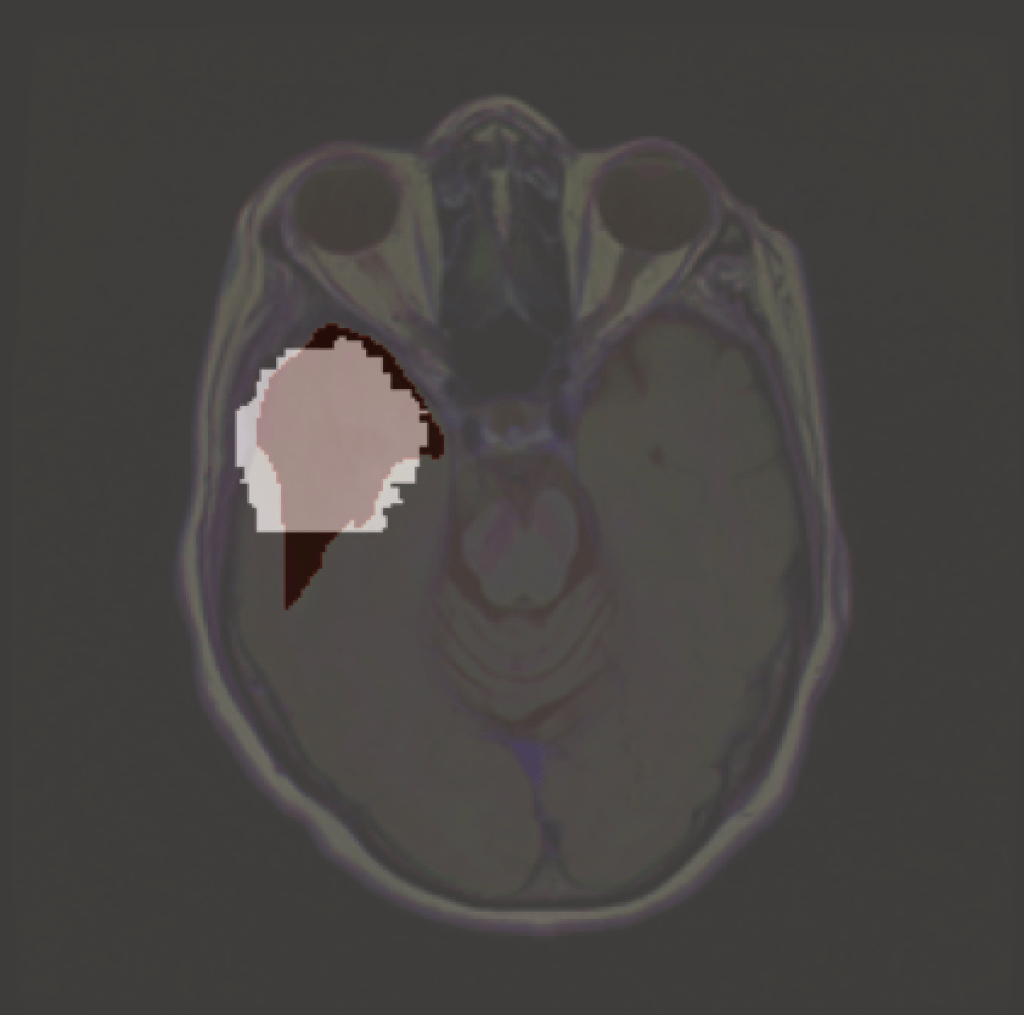

Continue reading →: Explanations of AbsenceExplainable AI is any process in which we try to identify which features a model used in making a particular prediction. But what happens when we want to explain something that is defined by the absence of features? A model may learn that certain pixel characteristics are associated with a…